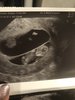

Ja już po wizycie. Wszystko wporzadku. Serducho bije, dzidzia ma już prawie 4 cm. [emoji7]

Zobacz załącznik 1066251